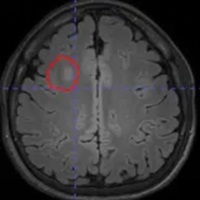

脑电图检查提示:右侧额叶异常放电。但常规头颅磁共振检查,始终未能发现明确的致痫病灶。面对这种情况,只能先通过药物控制病情。

借助医院先进的高清晰度、高对比度薄层扫描核磁共振,配合PET-CT检查,终于在右额叶发现了一个极其微小的致痫病灶。这个位置,与脑电图提示、以及临床发作特征完美吻合。更幸运的是,虽然病灶位置深,但范围很小。